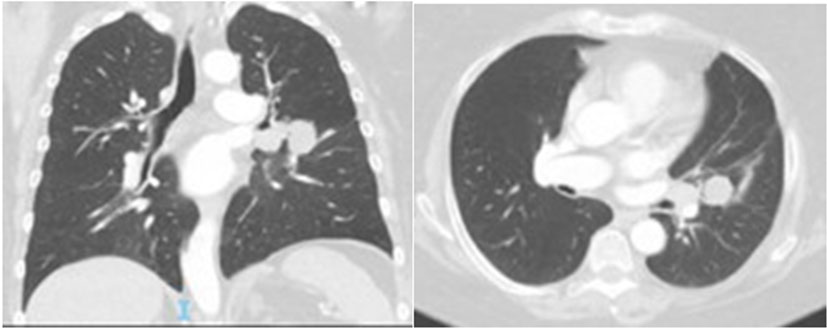

Based on the revised histopathology report, the chemotherapy was changed to carboplatin and gemcitabine. Although the hemoptysis resolved, she was commenced on nivolumab due to clinical progression. She completed seven cycles up until October 2019. Unfortunately, there were multiple treatment delays due to an episode of infective colitis followed by immune-related colitis confirmed on colonoscopy requiring intermittent use of high dose steroids. Despite this, she gradually improved clinically with associated improvement in functional status. This was radiologically confirmed on repeat restaging scan which showed near complete response (Figure 4). She remains stable on the most recent scan from 25th May 2020.

Figure 4: Progress CT chest (18 October 2019)—near complete response, showing residual lung lesion after 7 cycles of Nivolumab from 30 April 2019.